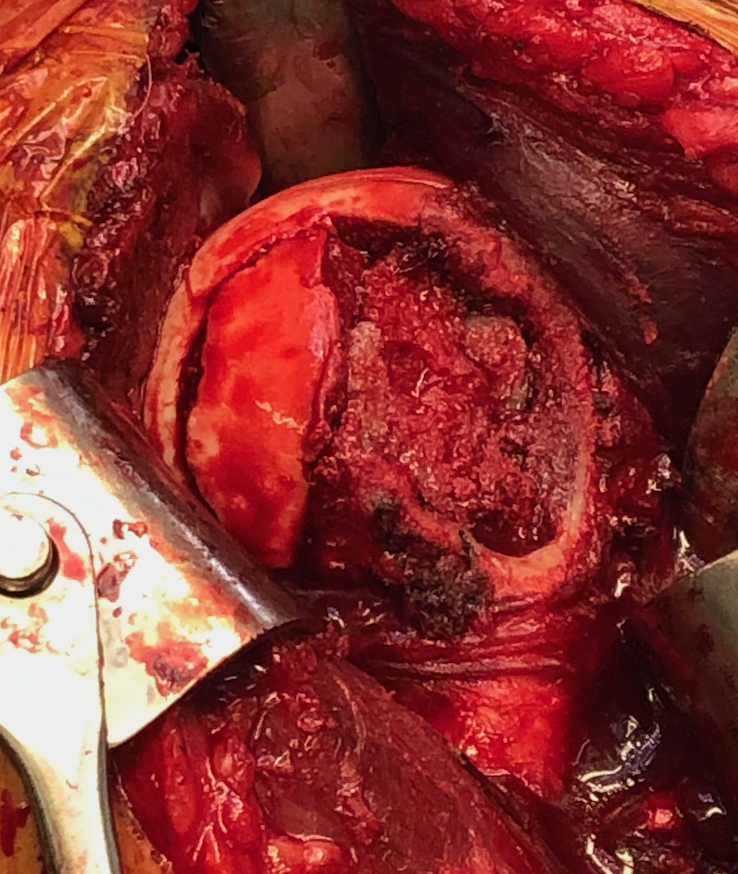

Case 1: Lesser tuberosity osteotomy, removal comminuted articular fragment, insertion osteochondral allograft

Case 2: Osteochondral allograft with anchor repair of subscapularis